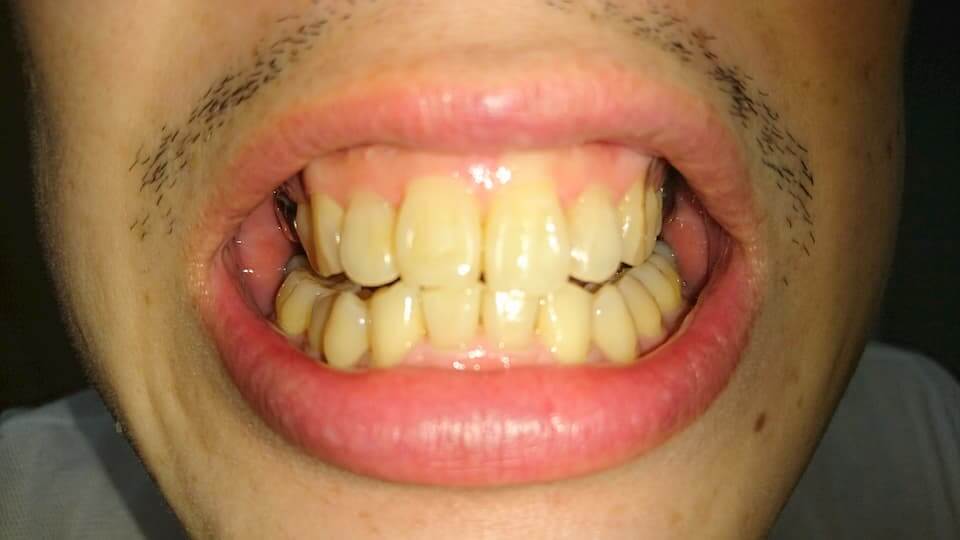

歯の写真

下の第1、2小臼歯辺りがマウスピースをはめていても痛かった。

外すと歯が戻ろうとするのか犬歯から大2大臼歯辺りまで痛みが出る。

まだ歯の位置が定着していないみたい。